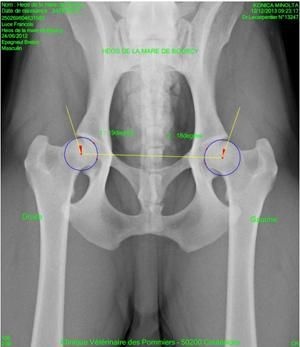

Qu'est ce que la dysplasie coxo-fémorale (Hips Dysplasia, HD)?

La dysplasie de la hanche, ou dysplasie coxo-fémorale, est une affection très fréquente dans l’espèce canine.

Elle provient d’une malf...